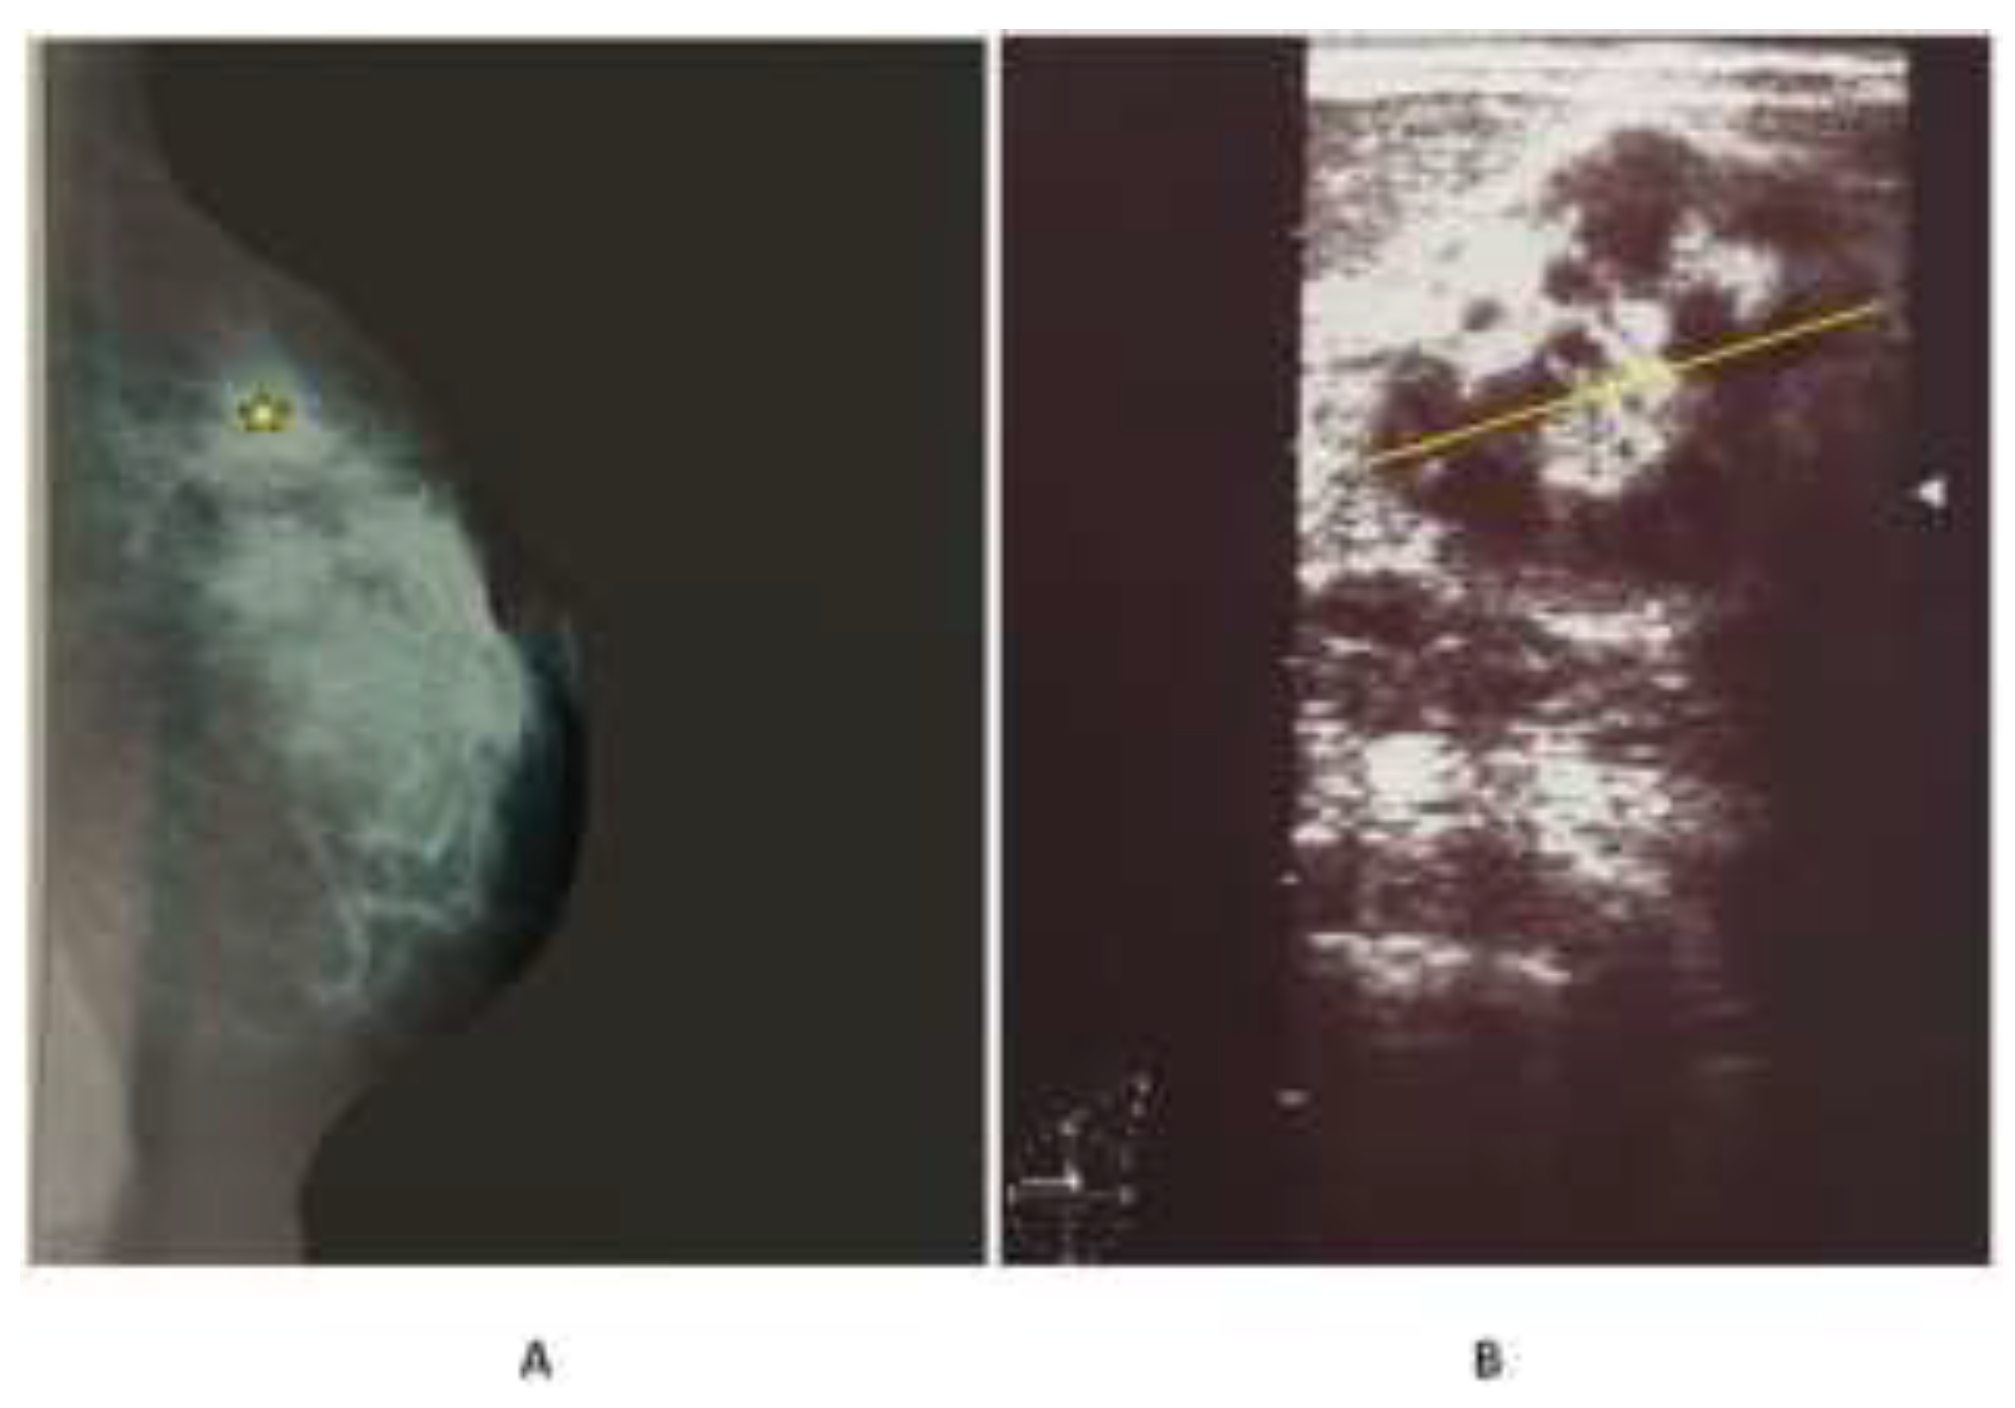

- Ozsoy, A.; Dolek, B.A.; Barca, N.; Aktas, H.; Araz, L.; Kulacoglu, S. Ultrasound Findings in a Case of Myeloid Sarcoma of the Breast. J Belg Soc Radiol. 2016, 100, 15. [Google Scholar] [CrossRef] [PubMed]

- Nishida, H.; Kinoshita, T.; Yashiro, N.; Ikeda, Y.; O’Uchi, T. MR findings of granulocytic sarcoma of the breasts. Br J Radiol. 2006, 79, e112–e115. [Google Scholar] [CrossRef] [PubMed]